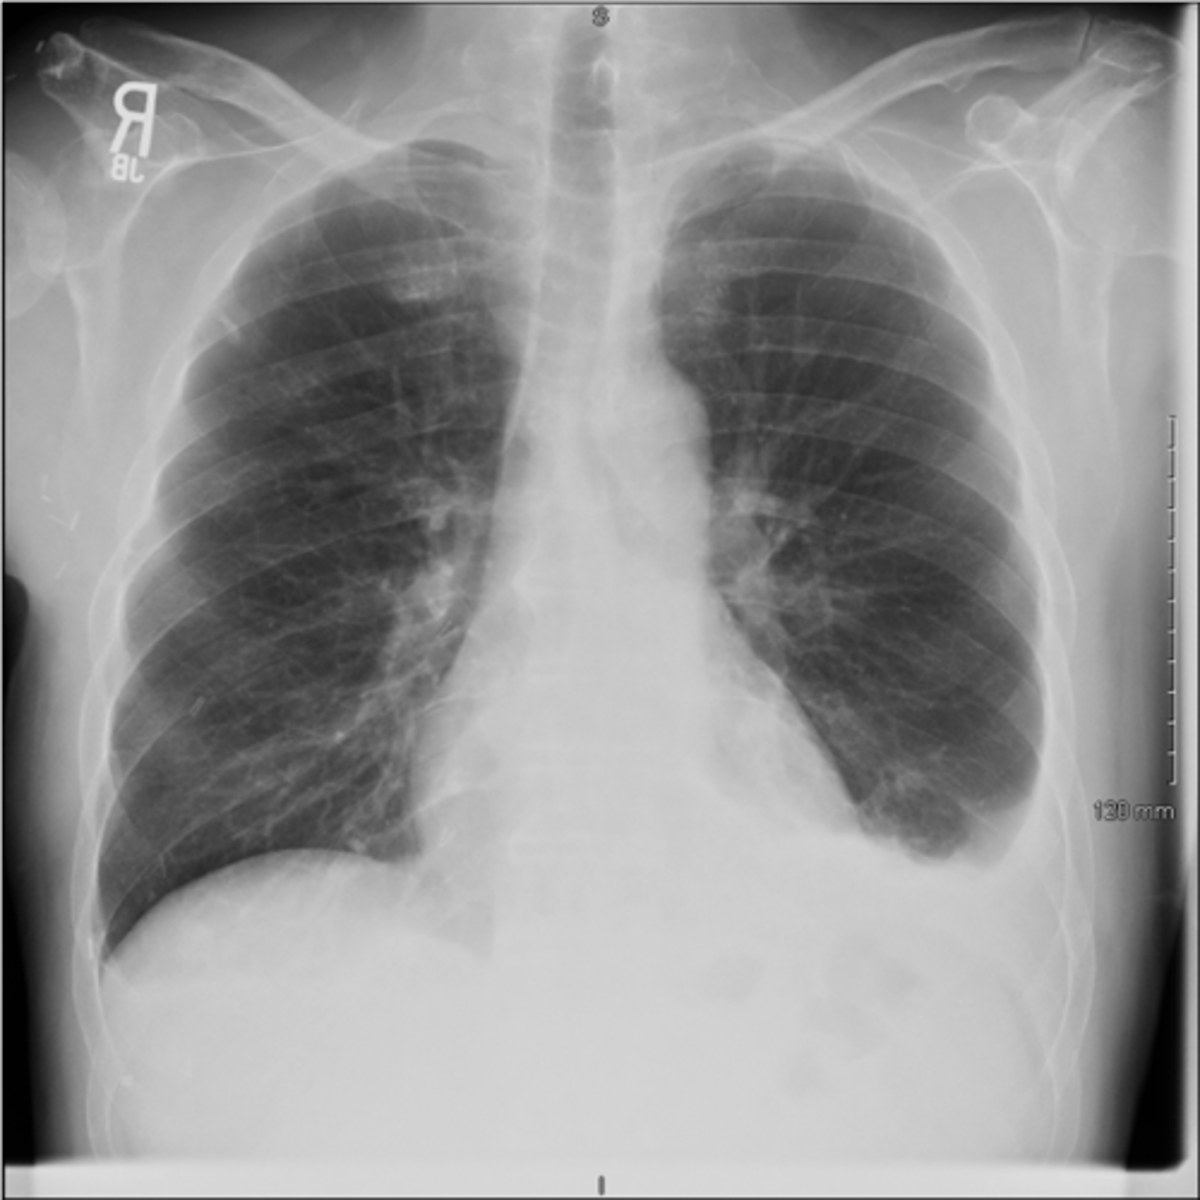

CXR in affected individuals is often normal or shows non-specific findings

Bronchiectasis